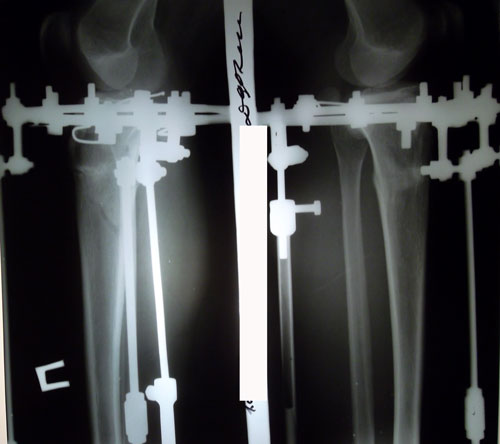

рентген на 15 -ый день после операции.

20151219_113113.jpg

20151219_113253.jpg